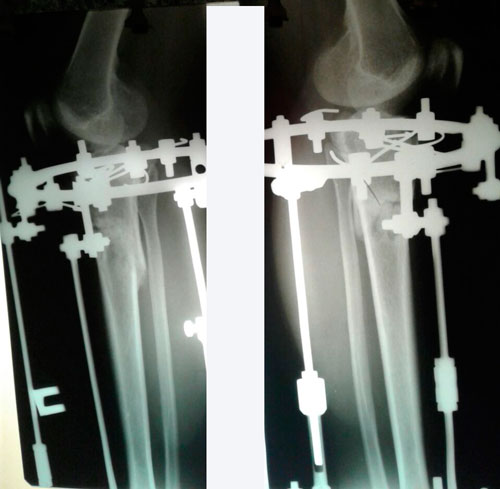

Дата операции 31.08.2016г.

Дата снятия аппаратов 25.11.2016г.

Срок лечения 84 дня.